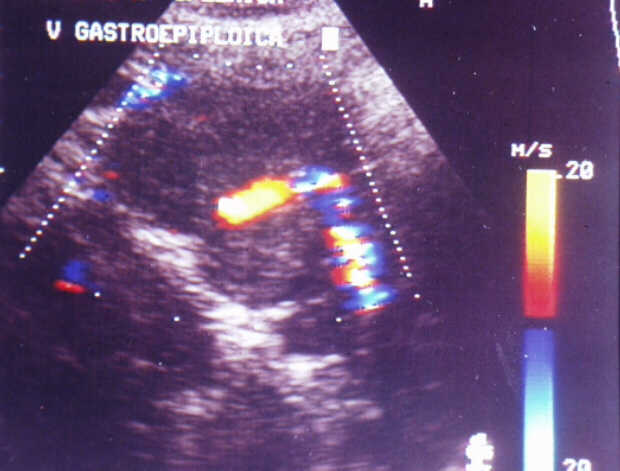

Diagnosis: Angiography

Giuseppe Morelli Coppola, Raffaella Niola, Franco Maglione

Unità Operativa di Radiologia Vascolare ed Interventistica, Azienda Ospedaliera "A. Cardarelli". Napoli, Italy